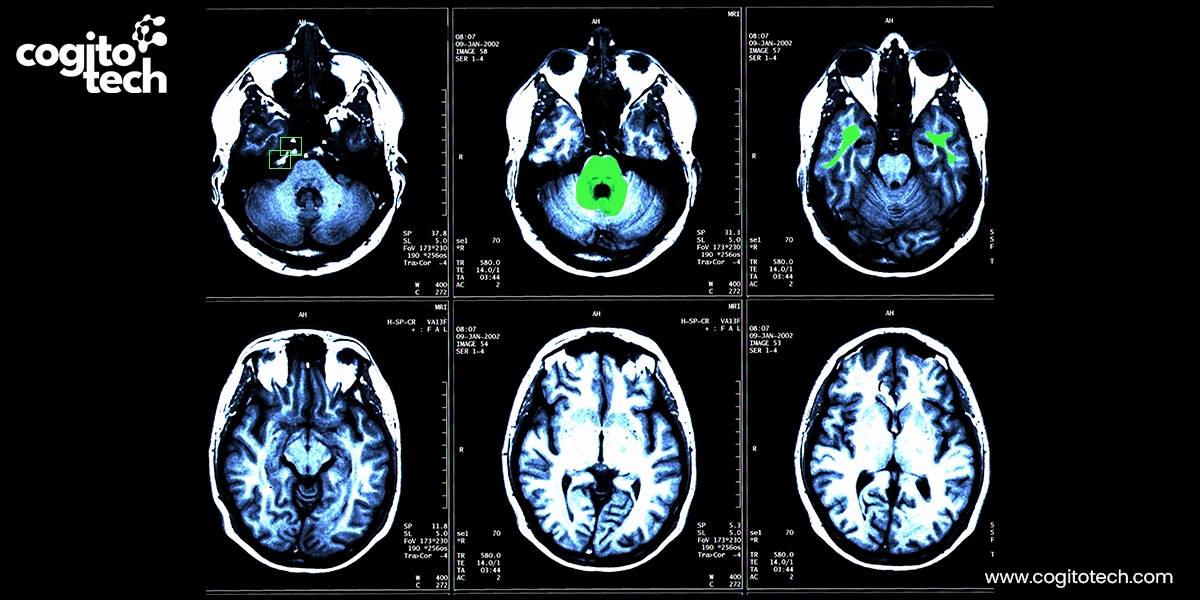

Cardiac imaging annotation

- Cardiac MRI: This involves segmenting the ventricles, atria, myocardium, and pericardial fat, as well as labeling tissue characteristics such as late gadolinium enhancement (LGE) scars. These annotations help AI models analyze cardiac function, fibrosis, and metabolic risk.

Structured labeling of cardiac MRI and late gadolinium enhancement (LGE) images – covering myocardial tissue properties, scar regions, and key anatomical landmarks – supports deep learning models for automated scar quantification, arrhythmia focus localization, and ablation strategy planning. These annotations also enable real-time guidance systems and robotic-assisted interventions by improving anatomical mapping and reducing fluoroscopy exposure. High-quality, clinically validated annotations are critical for training scalable and reliable AI models in electrophysiology imaging applications.